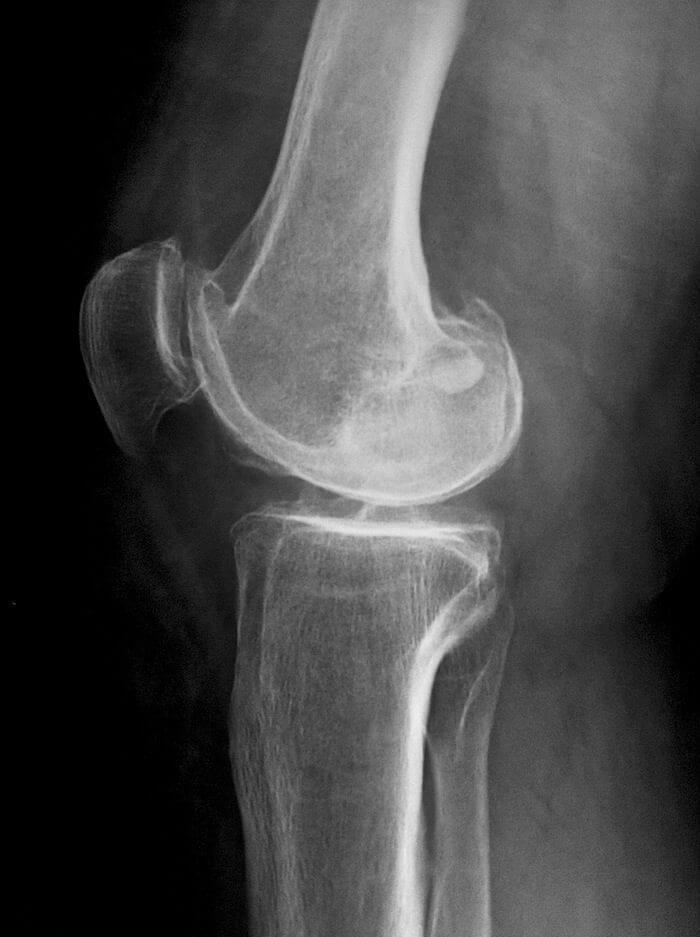

- Рентген. Позволяет оценить состояние костных структур. Хрящевую ткань практически не визуализирует.

- КТ. Снимки совершаются в разных проекциях под определенными углами. Этот метод позволяет досконально визуализировать не только костные, но и хрящевые структуры.

- МРТ. Процедуры выполняется с использованием специального оборудования основанного на воздействии на организм человека электромагнитного поля.